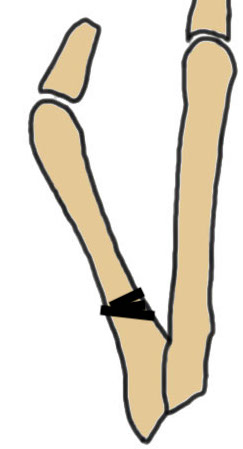

Coughlin Classification

| Type I | Type II | Type III |

|---|---|---|

| Prominent lateral condyle 5th metatarsal head | Lateral bowing of 5th metatarsal |

Increased 4/5 intermetatarsal angle Normal 5 degrees 5th metatarsal straight |

| Lateral condylectomy | Osteotomy | Osteotomy |

Lateral bowing of 5th metatarsal

Increased intermetarsal angle (IMA). Normal is 5 degrees

Osteotomy

Proximal

- Coughlin sliding oblique midshaft osteotomy

- proximal medial closing wedge osteotomy

- Scarfette osteotomy